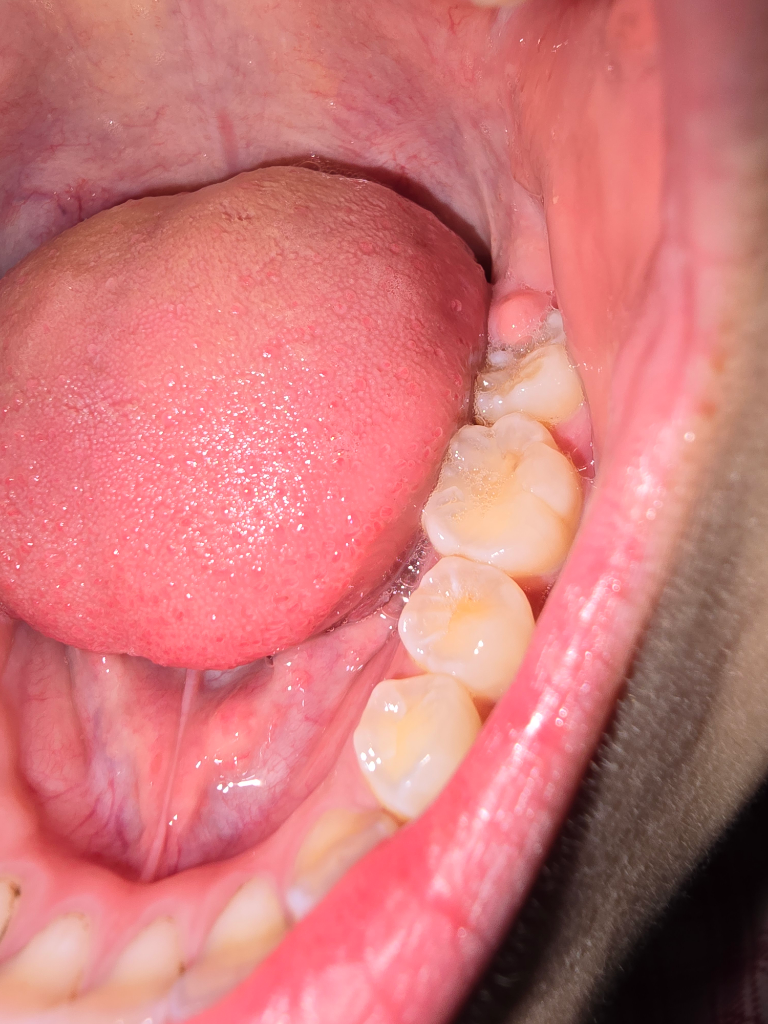

치아홈메우기..잇몸조금덮혀있어도되나요

1. 맨뒤 치아

저정도에서 홈메우기 되나요? 잇몸이 아예 안덮어야되나요

2. 맨뒤 앞 치아

어금니 표면 약간 거뭇한 부분 충치일지..아니면 착색일지요

잇몸이 덮여 잇다면 치아 홈메우기를 하기는 어렵지만 하게된다면 잇몸을 짤라 내고 해야될수도 잇습니다. 표면은 치아가 착색이 된거 같습니다 .

지금상태에서는 홈메우기 치료를 하기는 힘들며 사진상 특별히 충치가 보이지는 않습니다.

실란트를 하기 위해서는 잇몸이 치아 밖으로 나와 있어야 합니다. 뒤에 있는 지어낸 실란트를 하기에는 아직 이를 것으로 생각됩니다. 앞의 치아는 충치라기보다는 부분적으로 착색이 된 것으로 보입니다. 자세한 확인을 위해서 치과에서 진료를 받아보는 것을 권유드립니다.

1. 특별히 실란트(치아 홈메우기)가 필요한 치아로 보이지 않습니다.

3. 실란트의 경우 주로 치아 홈이 깊게 파인 경우, 양치질 습관이 아직 덜 잡힌 어린이들에게 적합하며 충치가 없는 치아여야 합니다.

4. 6번치아 (뒤에서 두번째 치아)는 충치의 양상은 아닌 것 같습니다

5. 잇몸에 약간 파묻혀 있는 7번치아(맨 뒤 치아)는 만약 실란트를 하고자 하는 경우 잇몸을 조금 절개해줄 수도 있습니다.